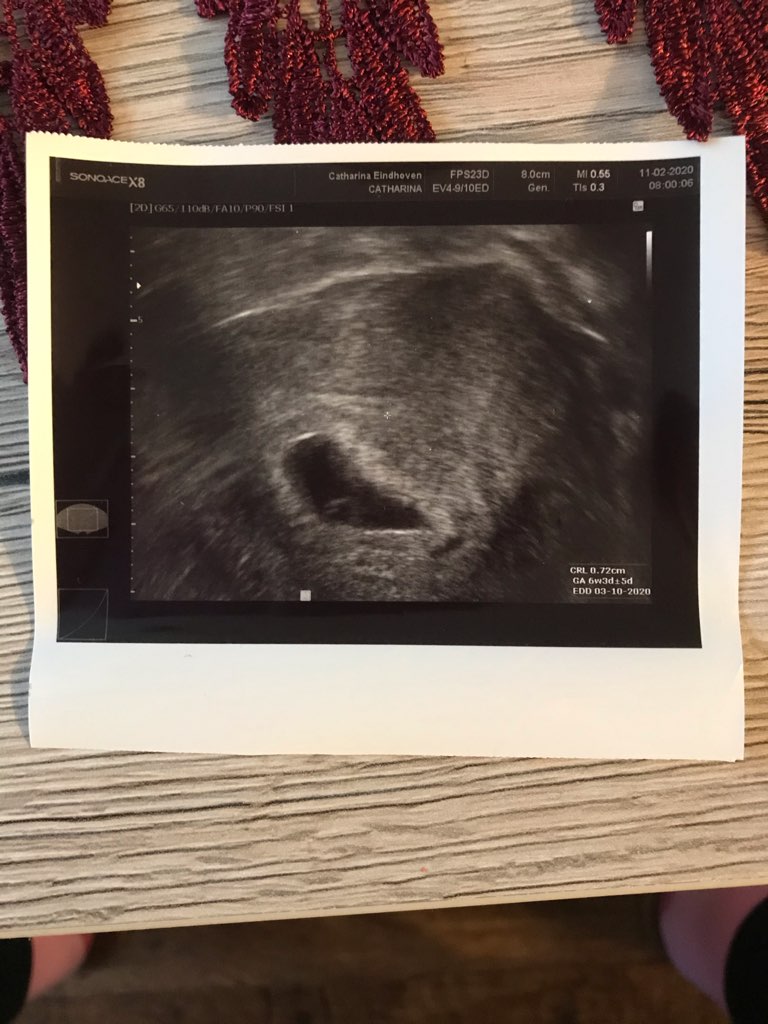

u mnie w 26dpt dopiero co majaczył zarodek, nawet nie szło go zmierzyć. W 33dpt piękny zarodek z sercem pomiędzy zdjęciami jest tydzień różnicy pierwsze 26dpt i drugie 33dpt jeśli jest pecherzyk zoltkowy jutro już powinien być zarodek

• IMG_1882.jpeg

IMG_1882.jpeg

120,9 KB · Wyświetleń: 103